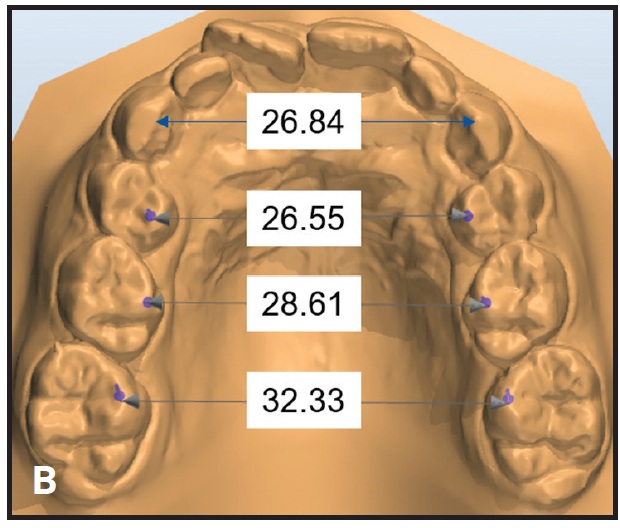

Fig. 3 Case 1. A. 6-year-old male patient with maxillary transverse deficiency, crossbite, mandibular deviation, and missing upper right central incisor (extracted at age 4) before treatment. (Panoramic radiograph taken seven months earlier.) B. Arch-width measurements on STL digital cast obtained from laboratory scan of polyvinyl siloxane impressions.

Fig. 7 (cont.) Case 2 B. Arch-width measurements on STL digital cast obtained from laboratory scan of polyvinyl siloxane impressions.